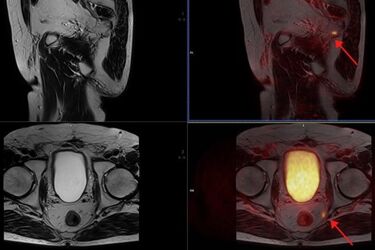

Fot: BioSkaner. Widoczny przerzut o średnicy 4 mm do węzła chłonnego miednicy mniejszej

- Uniwersytet prowadzi nowy projekt naukowy dla osób chorych na raka gruczołu krokowego (RGK) przy użyciu innowacyjnego radioznacznika 18F-PSMA. W ramach projektu pacjenci mają bezpłatny dostęp do wysoce innowacyjnych i niedostępnych na rynku badań PET/MR całego ciała z bardzo swoistym znacznikiem 18F-PSMA - wskazuje Marcin Tomkiel, rzecznik prasowy Uniwersytetu Medycznego w Białymstoku.

Tomkiel tłumaczy również, że dzięki wykonaniu wspomnianego badania, specjaliści są w stanie wykryć nawrót choroby na bardzo wczesnym etapie, a to oznacza szansę na szybsze podjęcie dalszego leczenia.

Komercyjna cena wykonania badania PET/MR to 6,5 tys. zł. Więcej informacji można znaleźć na stronie internetowej wykonawcy badań - pracowni BioSkaner.